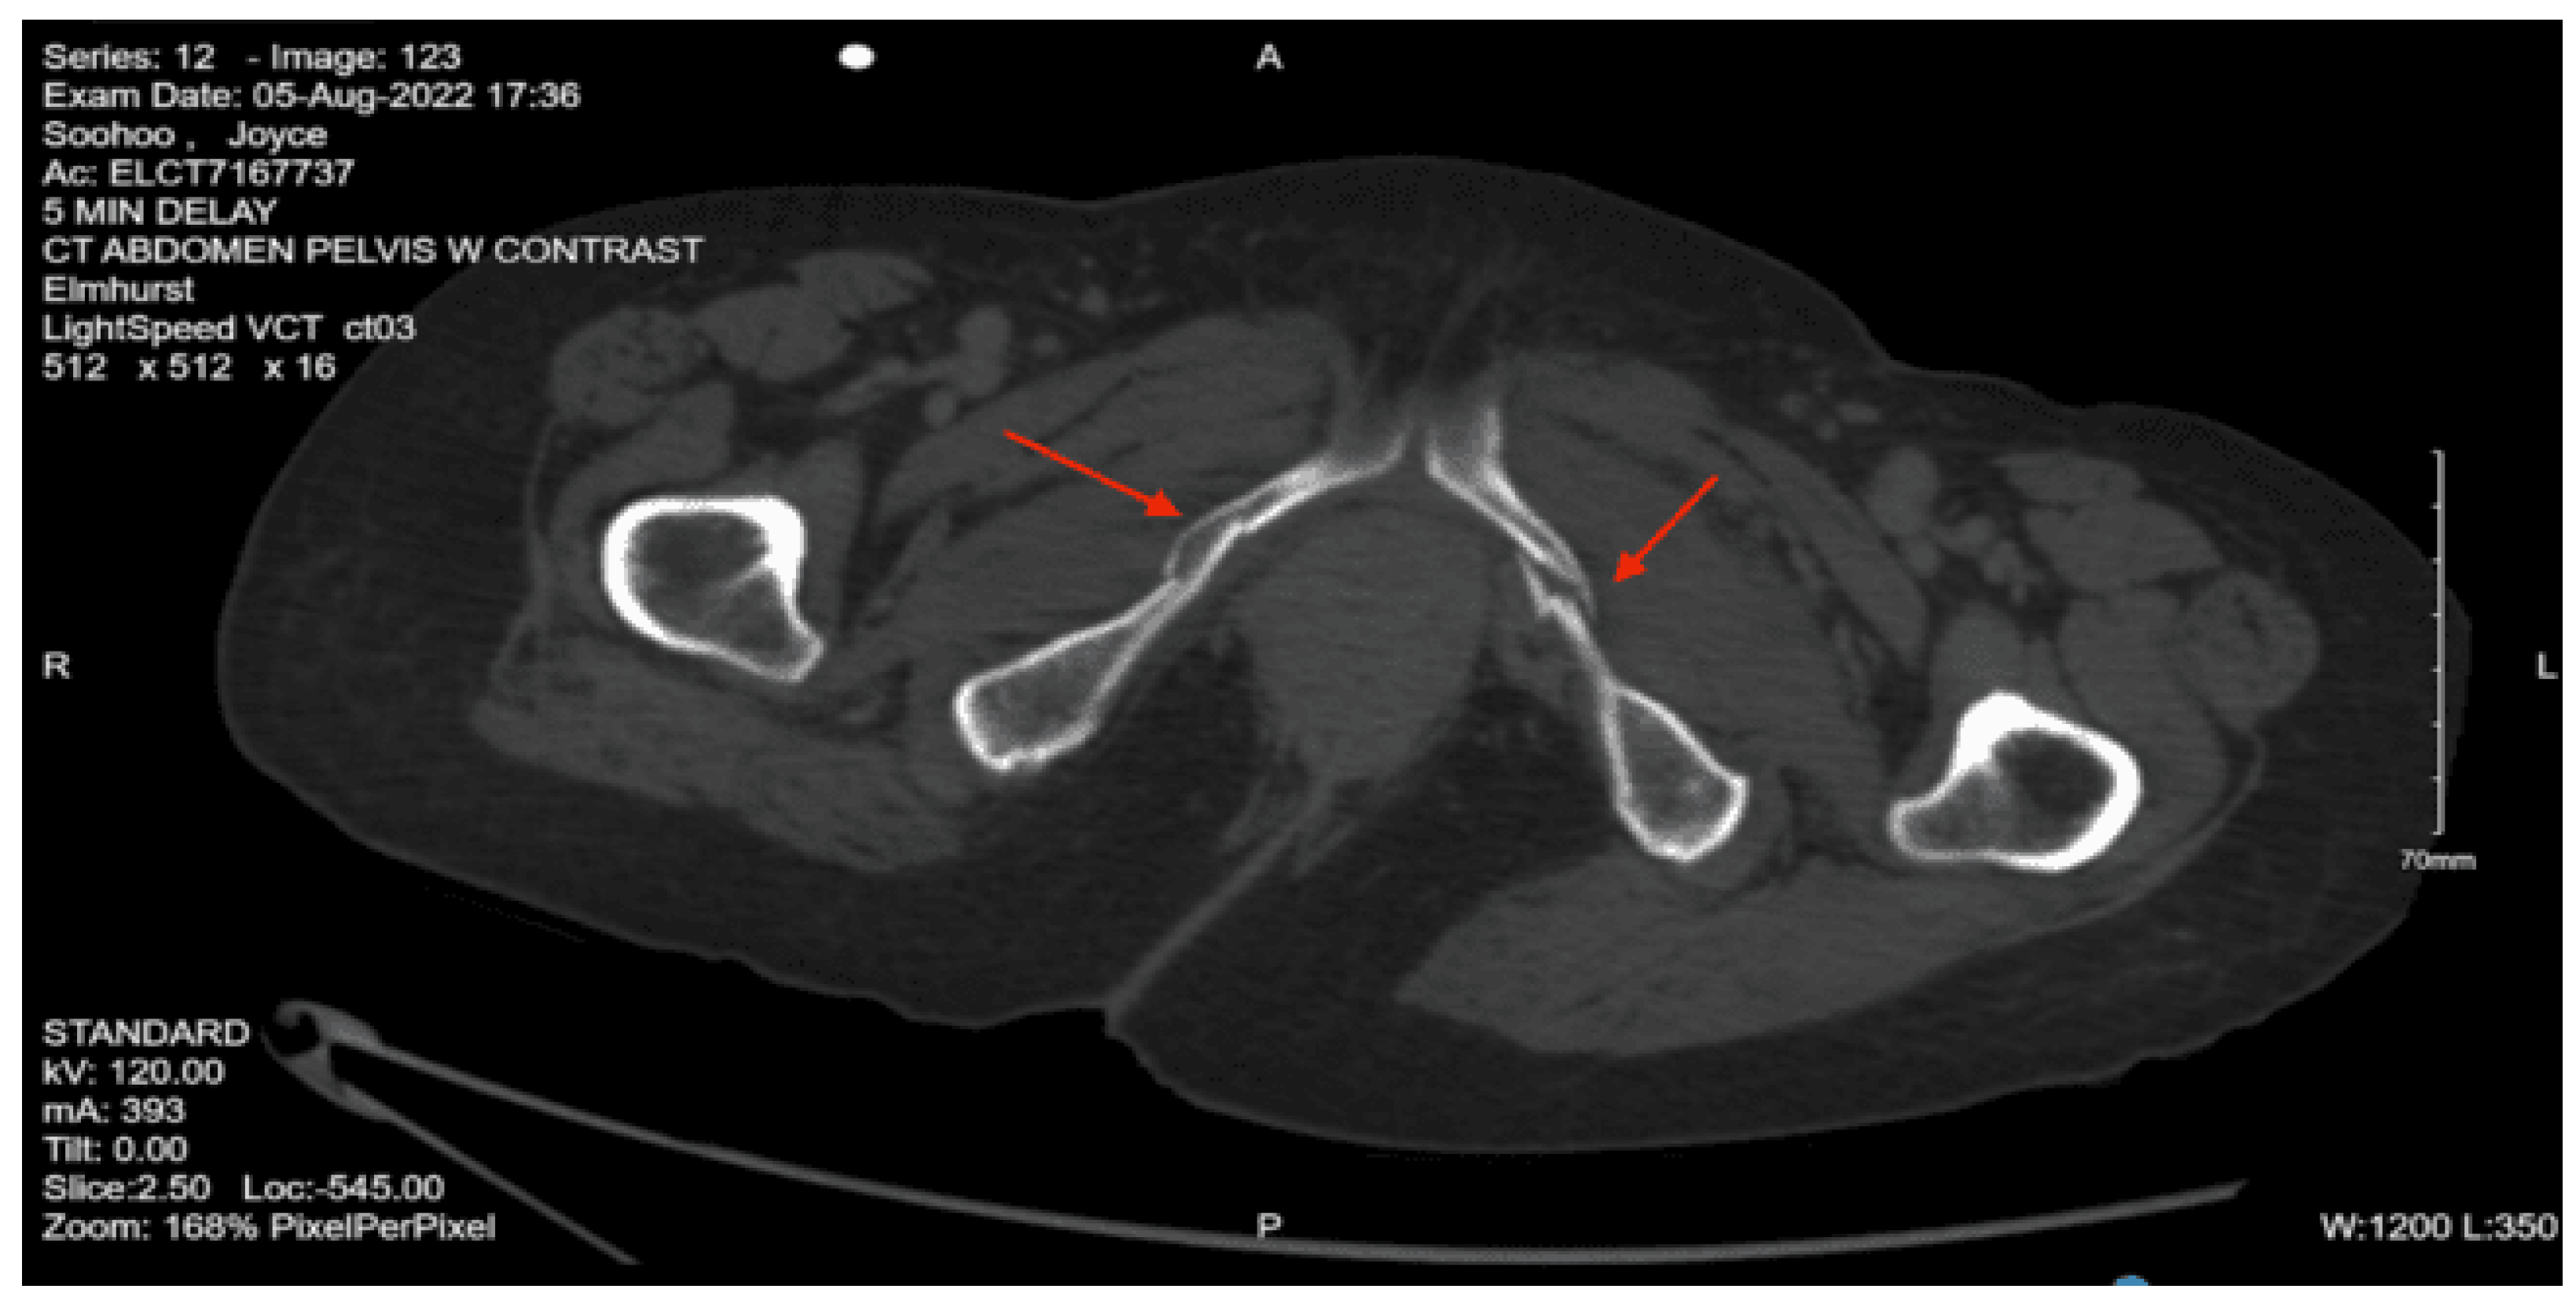

On secondary evaluation, the patient’s pupils were equal, round, and reactive to light. He had left eyelid swelling and ecchymoses. His extraocular movements were intact. The patient had some dried blood in his nares with no nasal septal hematomas. His chest and back had no obvious deformities and were non-tender to palpation. His spine did not have any step-offs or palpable deformities. His abdomen was soft and non-distended but had some suprapubic tenderness to palpation. The patient was moving all four extremities spontaneously. He had ecchymoses to the left elbow and had significant swelling and tenderness to palpation. His left lower extremity was shortened and externally rotated. A left knee abrasion and tenderness to palpation at the left hip and foot were present. His E-FAST was negative, and portable chest and pelvis x-rays were done, which showed multiple pelvic fractures, so a pelvis binder was placed.

Portable chest x-ray: no traumatic findings.

Portable pelvic x-ray: comminuted fracture of the left pubis and adjacent superior and inferior pubic rami. Left femoral neck fracture with no dislocation.

CT abdomen pelvis with contrast: Left sacrum nondisplaced fracture extending through the neural foramina throughout its entirety. Mild widening of the SI joint. Incomplete hairline fracture of the iliac bone medially just above the acetabulum. Left pubis, most medial superior ramus, and more extensive left inferior pubic ramus fractures. Comminuted fracture of the left femoral neck. Anterior perivesical and left pelvic hematomas.